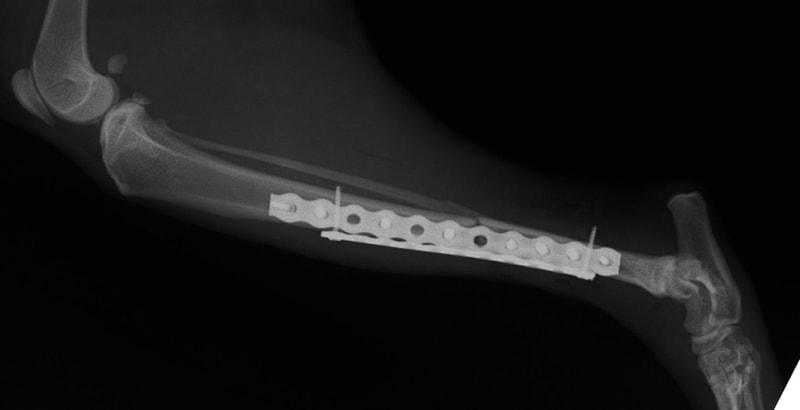

症例3:キルシュナーワイヤーのピンニングによる整復

ペルシャ猫 11ヶ月齢 雄

他院にて左大腿骨遠位の成長板骨折(salter-harrisⅠ型)が認められており、治療相談を目的として来院。当院にて、キルシュナーワイヤーを用いたピンニングにより骨折部位の整復を行いました。術後の経過は良好で、現在も経過観察中です。

術後レントゲン

Arthrex社のターゲティングデバイスを用いてピンニングの位置を調整することで、確実な固定を行っています。当院ではこの手術器具以外にも、人の手術にも使用される様々な器具を導入し、手術精度を高め、また医療メーカーと新しい器具の開発、試作にも取り組んでおります。